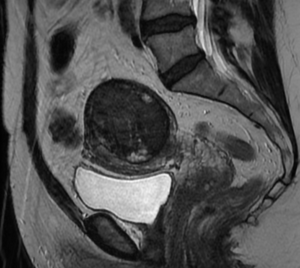

Uterine Fibroid Embolization